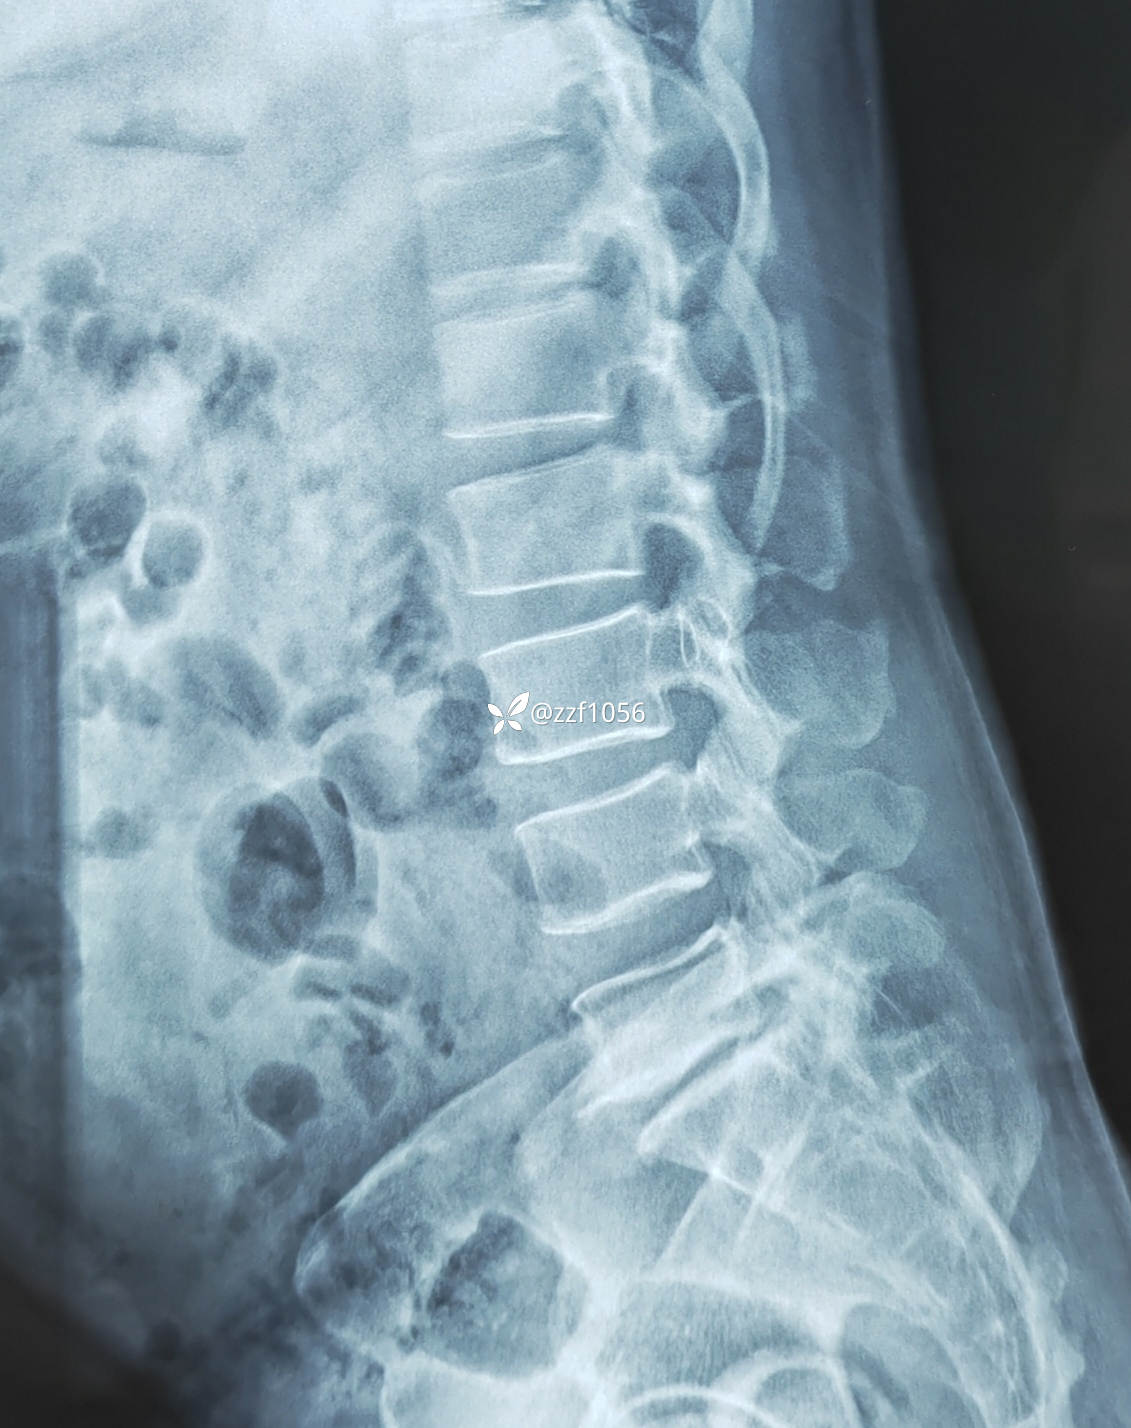

症像不符的一例腰椎间盘突出症,是否考虑极外侧突出,减压融合后效果良好

【临床诊断】:腰椎间盘突出症 终板炎

影像上可看到L5/S1间隙非常狭窄,退变严重,两侧均有神经根激惹,椎间孔狭窄,L5下终板终板炎较重,左下肢无任何症状,右下肢L5S1根症状均存在,建议椎间孔镜下减压L5根和S1根,患者拒绝,因咨询多家医院要求开放融合。